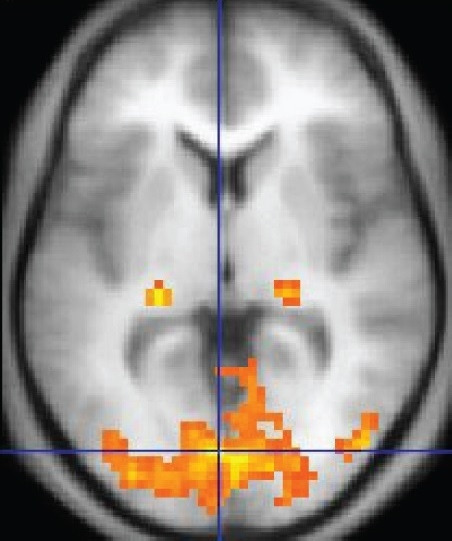

fMRI라는 기계 (혹은 방법론)에 대해 많은 사람이 들어 보았을 것이다. 인간이 어떤 감각을 느끼거나 어떤 생각을 할 때, fMRI가 실시간으로 생각과 뇌의 구역에 대해 1대 1 매칭을 해 준다. 우리는 무엇을 볼 때 뇌의 뒷부분이, 들을 때 옆부분이, 몸을 움직이거나 움직이는 것을 생각할 때 윗부분이, 감정을 느낄 때 뇌의 속이, 그리고 계획을 세우거나 복잡하고 고차원적인 무언가를 상상할 때 뇌의 앞부분이 활성화된다는 사실을 바로 이 기계를 통해 알게 되었다. 심리학과 인지과학, 뇌과학의 총아이자, 뇌와 우리가 도대체 무슨 관계인지를 밝혀내고자 하는 과학자들에게 적절히 다가온 최고의 실험도구이다. TV에서 실험가운을 입은 전문가가 뇌의 단면에 노랗고 빨갛게 색칠된 슬라이드를 보여주며 "뇌의 이 부분이 이러저러해서 우리는 느끼고 행동합니다."라고 말할 때, 우리는 미래를 느끼고 뇌의 신비에 한 걸음 다가간다. 느낌만이라도.

fMRI 측정 장면, fMRI 결과 예시